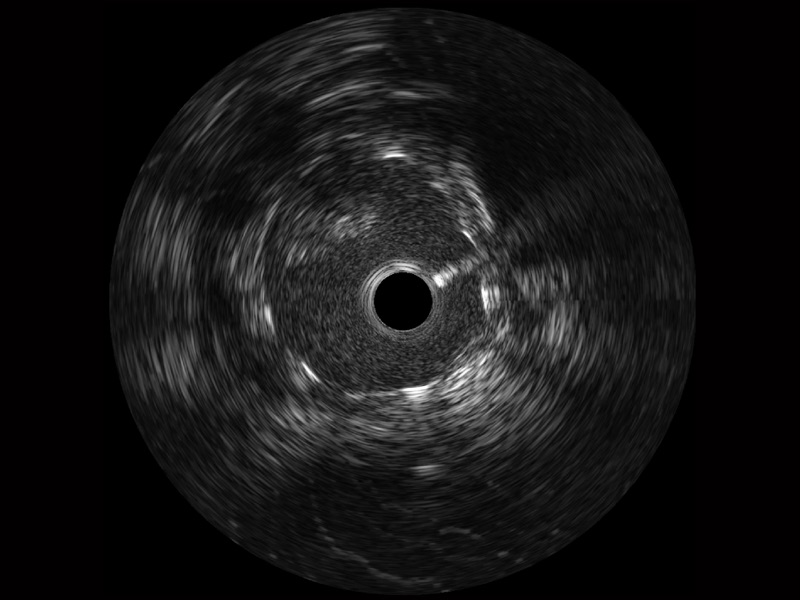

环球UG官网宽频IVUS图像

传统IVUS图像

对比传统IVUS导管成像,环球UG官网宽频IVUS图像的近场支架梁显影更细腻,远场中膜外血管仍清晰可辨,兼顾远中近,兼顾分辨力与穿透深度